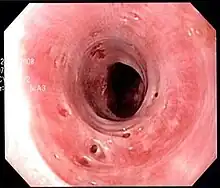

| Endoscopic image of esophageal intramural pseudodiverticulosis demonstrating the flask-like outpouchings of the esophageal wall. | |

Esophageal intramucosal pseudodiverticulosis is typically diagnosed at the time of endoscopy of the esophagus. Endoscopy shows evidence of the pseudodiverticulae, which are typically numerous, appear like pits in the wall, and may be preferentially located in the upper esophagus.[3][5] The mucosal lining of the esophagus may be inflamed, and this can be seen on endoscopy or on biopsy; the mucosa, however, may also be normal if esophagitis is not the cause of the pseudodiverticulosis. The condition must also be excluded from esophageal cancer, which may be done at the time of endoscopy, or which may require esophageal biopsy.[3]